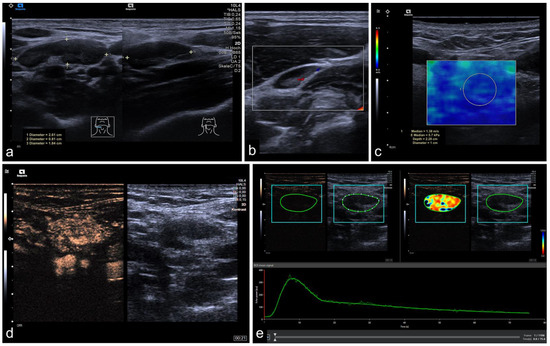

2.2. Imaging Protocol

2.3. Perfusion Analysis